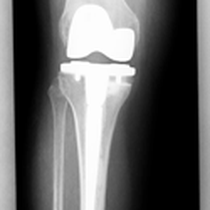

Auch bei dem künstlichen Ersatz des Kniegelenkes muss genau abgewogen werden, was eingentlich ersetzt werden muss. Je weniger ersetzt wird umso besser im Gesamtergebnis. Warum soll man das ganze Knie ersetzen, wenn nur der Knorpel unter der Kniescheibe zerstört ist (Bild 3 Kniescheiben - und Gleitlagerersatz). Anders bei schwerer Rheumazerstörung, bei der alle Bänder ausgelockert sind - hier wäre die normale Knieprothese auch locker (Bild 5 Lösung: achsgekoppelte Prothese). Ich versuche für meine Patienten das bestmögliche Implantat auszusuchen. Für Allergiker stehen spezielle titanbeschichtete Kniegelenke zur Verfügung.